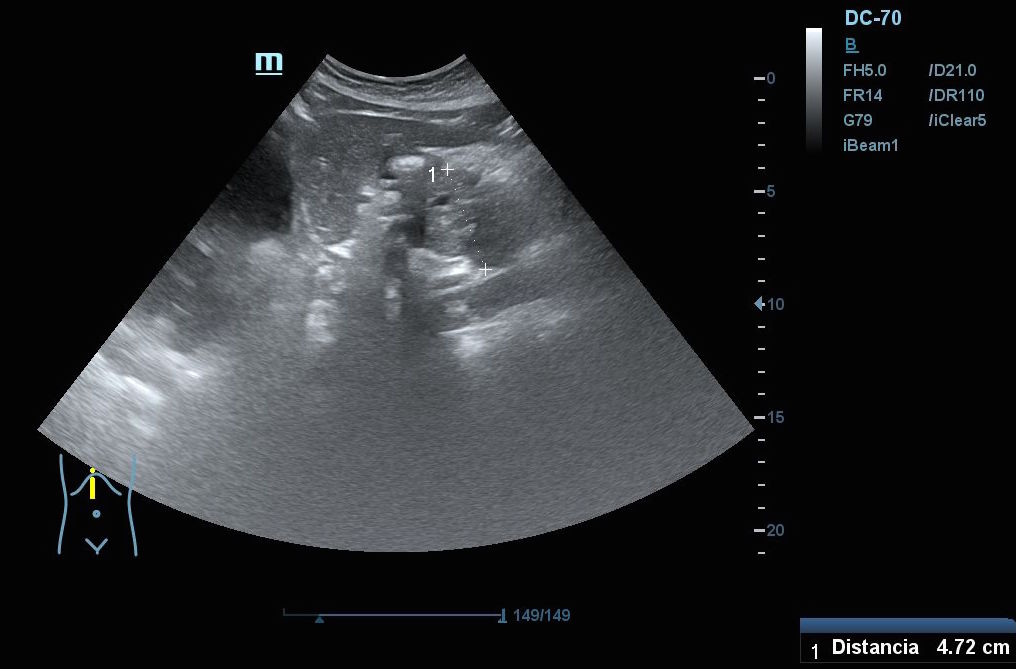

Hallazgos ecográficos: En el epigastrio se observa una imagen anecoica tubular, sin captación en Doppler, con un diámetro mayor a 2 cm, que sugiere una dilatación del colédoco (imagen 1). La vesícula biliar se encuentra completamente distendida y hepatizada, con una imagen en «doble cañón de escopeta» sugestiva de colestasis (imagen 2). En los cortes longitudinales se identifica una masa anterior a la aorta en el corte paramedial izquierdo, aparentemente localizada en el cuerpo del páncreas (imagen 3). En los cortes transversales se observa una masa que afecta tanto al cuerpo como a la cabeza del páncreas (imagen 4).